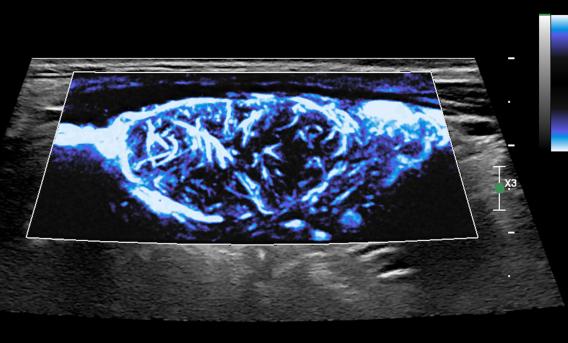

UTSW helps address common, chronic and underdiagnosed condition in women

CACTUS lab supported the roll out of a new pelvic ultrasound imaging protocol to screen for deep infiltrating endometriosis (DIE), a relatively common and sometimes debilitating disease.